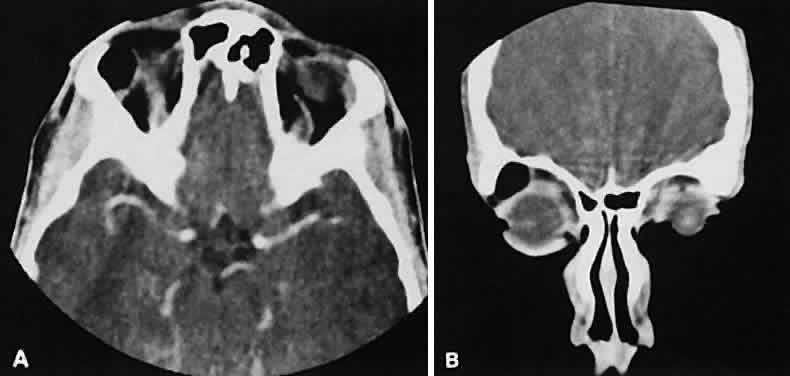

the inferior orbital fissure near the apex. Lesions that appear to change

size or shape from the axial view to the coronal view also have turned

out to represent a varix based on our experience (Fig. 2). Arterial lesions may either have high or low flow. The high-flow lesions are carotid cavernous sinus fistulas and result from a direct communication between the carotid artery and the cavernous sinus. These arise spontaneously or as a result of trauma. The orbit is involved as an innocent bystander, because all signs and symptoms of orbital involvement follow from the retrograde transmission of increased venous pressure from the cavernous sinus. EOMs generally are enlarged, as is the SOV. The ipsilateral cavernous sinus also is enlarged. Intercommunication between the cavernous sinuses also may account for the occasional bilateral findings. Low-flow lesions result from increased blood flow through the cavernous sinus, but the intracavernous carotid artery itself is intact (Fig. 3). These typically are dural-cavernous sinus fistulas. A high index of suspicion may be required to diagnose these, but a fairly stereotyped presentation is a unilateral red-eyed glaucoma with proptosis. Abduction weakness also may be present. Enlargement of one or more EOMs along with an enlarged SOV are noted with CT scanning. A small lesion may escape detection with CT scanning and require high-resolution MRI or even selective internal and external carotid angiography for diagnosis if a high degree of clinical suspicion exists. In a patient with a known dural fistula, a sudden and dramatic deterioration in the clinical picture may be seen with a thrombosis of the SOV.11 The radiographic picture, at least regarding the CT appearance, probably will not change. MRI can nicely show the thrombosis in the SOV.